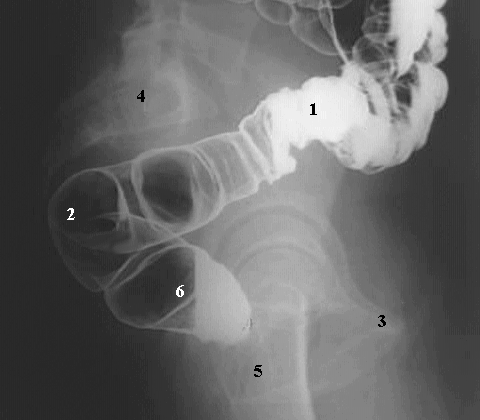

Abdomen - A C Barium Enema

1. Barium in the sigmoid colon

2. Sigmoid colon

3. Ischial tuberosity

4. Sacrum

5. Upper femur

6. Rectum